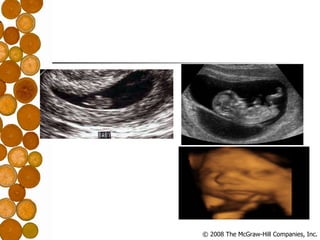

Prenatal Development Conception: Fertilization Zygote – fertilized egg Germinal Period: Weeks 1-2 Embryonic Period: Weeks 3-8 Fetal Period: Months 2-9

Prenatal Development Conception:Fertilization Zygote – fertilized egg Germinal Period: Weeks 1-2 Embryonic Period: Weeks 3-8 Fetal Period: Months 2-9